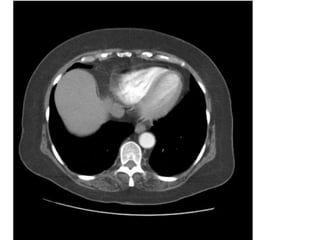

TRAØN DÒCH MAØNG PHOÅI

Nguyeân nhaân: Suy tim, vieâm nhieãm, u..

Hình aûnh

-Dòch ôû phía sau khi beänh nhaân naèm ngöõa

-Ñaäm ñoä dòch: cao trong chaûy maùu, dòch coù protein cao

-Maøng phoåi coù theå daøy, baét quang sau tieâm caûn quang

(daøy ñeàu trong vieâm, daøy noát thoâ, khoâng ñeàu trong u..)

Vai troø CT:

-Ñaùnh giaù möùc ñoä, loaïi (khu truù, töï do), vò trí traøn dòch

-Gôïi yù nguyeân nhaân (vieâm, u..)

-Phaân bieät: Traøn dòch maøng phoåi><Abscess phoåi ngoaïi

bieân